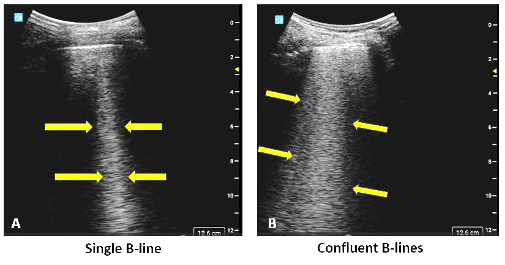

- B-lines: Vertical artifacts that arise from the pleura and suggest fluid in the lung, such as in interstitial or alveolar edema.

Figure 2. (A) A single (B-line) vertical hyperechoic artifact arising from pleural line and extending to the bottom of the screen away from the transducer footprint without fading in intensity. To demonstrate B-lines set the depth to approximately 12-15 cm. Image on the right (B) shows multiple confluent B-lines.